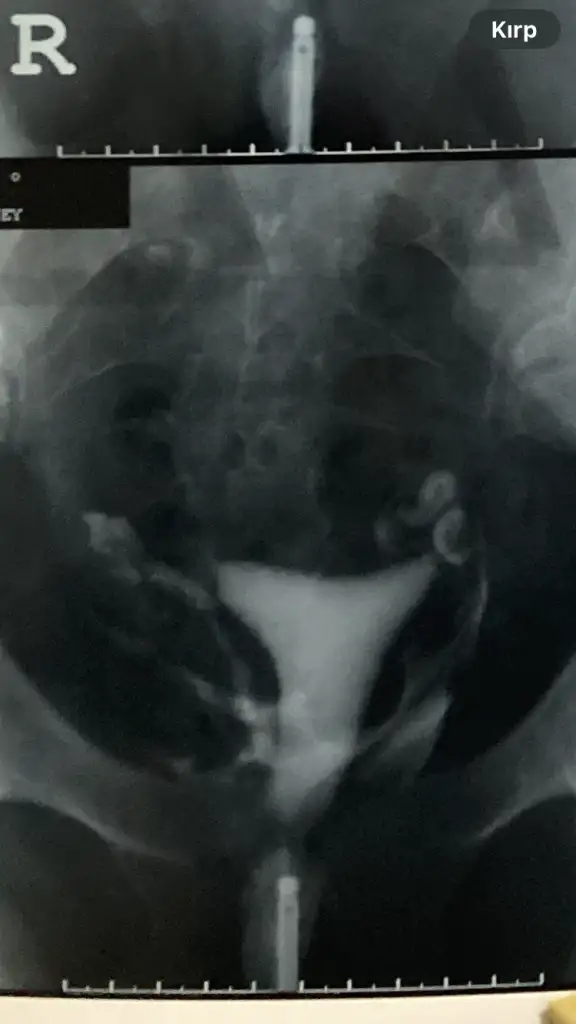

Valla bilemedim hidrosalpenks tıkanıp da içinde sıvı birikmesi. E hidrosalpenks demişlerse az da olsa bir tıkanıklık ve sıvı var demekki ve kendi icindeki sıvı yüzünden o tüpte gebelik oluşmayabiliyor eğer rahime geri sıvı akışı yapmıyorsa diğer tüple gebelik oluşur sıkıntı olmaz bence tabi doktorunuz sizin durumunuzu daha iyi bilir ben bu konu yüzünden her gördüğüm jinekologla konuştum resmen 1 aydır geceli gündüzlü bunu araştırıyorumKalınlık yazılmamış " tubalarda geçiş izlendi sol tüp hidrosalpinks? " Şeklinde yazılmış